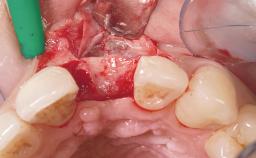

Immediate Placement of an Implant in a Maxillary Right Central Incisor Site

A 30-year-old female patient was referred to the office for the treatment of tooth 11. Her chief concern at the initial visit was to inquire, “Why is my tooth pink?” Upon clinical examination, it was determined that tooth 11 had a previous history of trauma and that the clinical crown had become noticeably pink in color as a result of internal resorption. This diagnosis was confirmed radiographically, indicating a large radiolucency involving the central and distal portions of the clinical crown. It was determined that restoration of this tooth was not possible, and that extraction was indicated. The presence of a mid-line diastema, which the patient wanted to reproduce, directed the treatment plan for tooth replacement utilizing a dental implant.

Bone Augmentation Horizontal|Simultaneous

Augmentation Materials Autogenous chips|Membrane

Soft Tissue Grafting None